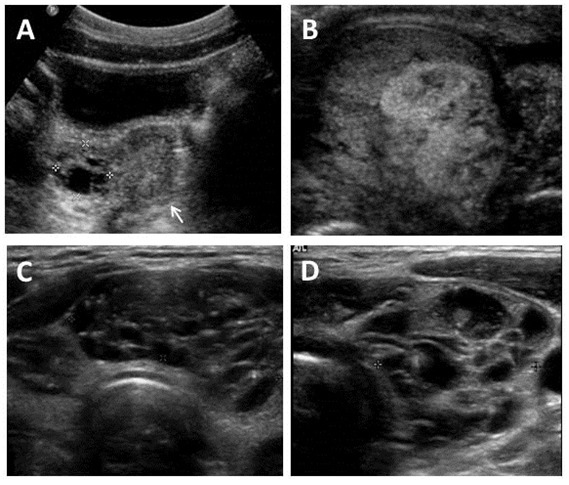

Figura 4. Imágenes ecográficas en el Síndrome de McCune-Albright

A. Ecografía pélvica en una niña de 7 años mostrando un quiste ovárico complejo unilateral (delimitado por las cruces). El útero tiene un tamaño prepúber (flecha).

B. Ecografía testicular en un adulto mostrando una lesión heterogénea con elementos mixtos sólidos y quísticos.

C&D. Hallazgos tiroideos ecográficos típicos del Síndrome de McCune-Albright incluyendo la apariencia heterogénea y quística (de “queso suizo”).